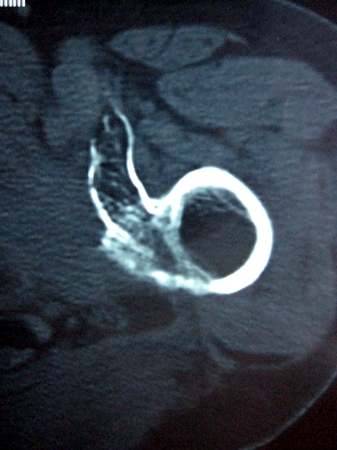

以下是引用lkc8963在2008-12-19 21:19:00的发言:[br]左?右?患侧大转子上移,股骨颈骨质浓杂,髋周见多发条片状骨化影,以小转子为著,多为陈旧性股骨颈骨折后改变并骨化性肌炎.请咨询既往史!